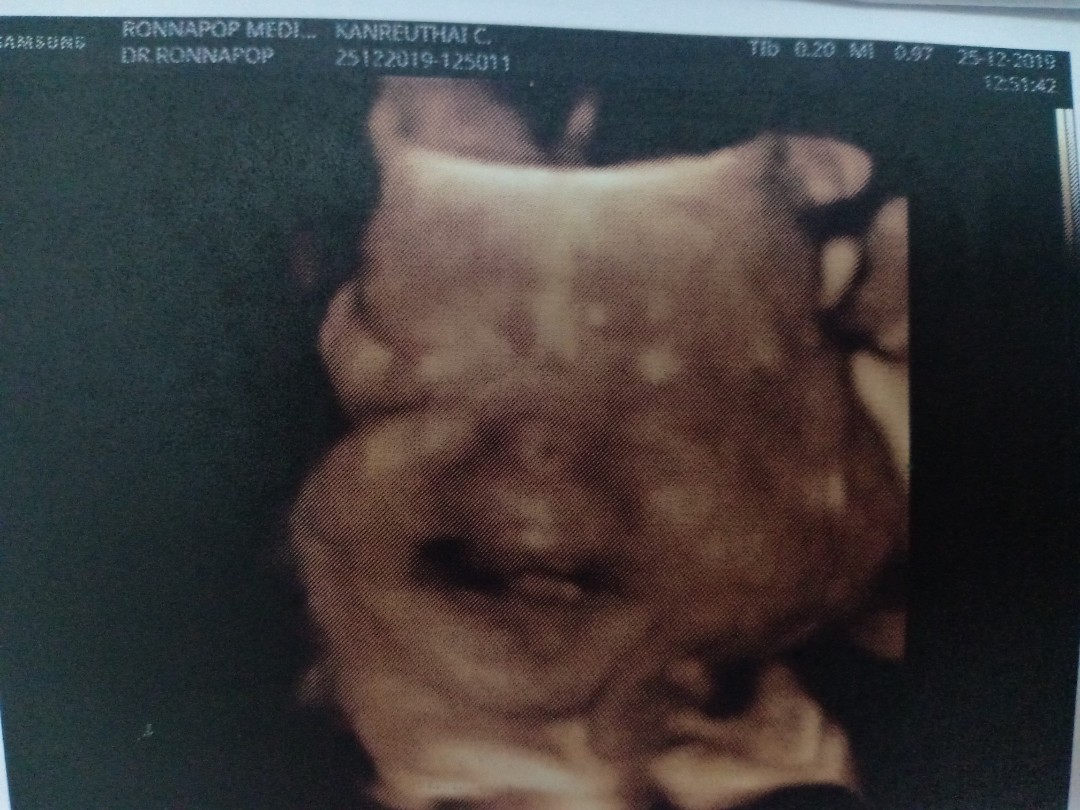

ลูกชายค่ะ 29 weeks 🥰

บ้านนี้ซาวตอน 28W จ้า

ซาวด์ตอน 31 w จร้าา